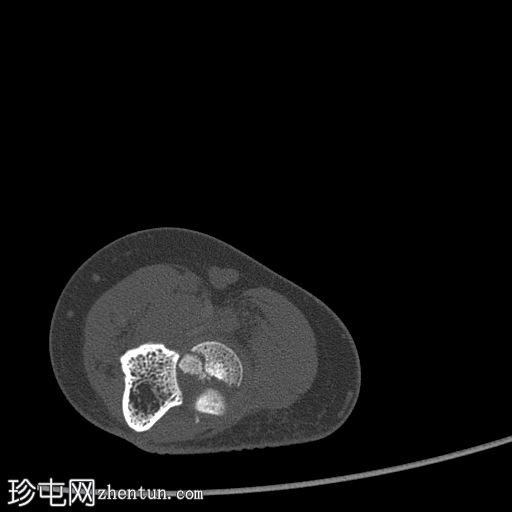

冠状面骨窗

显示整个桡骨头粉碎性骨折,特征为两个以上大骨折块,以及倾斜且受压的关节节。

这表明该骨折为不稳定骨折,根据Mason桡骨头骨折分型,为IIIC型。

远端肱骨和可见尺骨未见骨折征象。

此外,由于关节积血导致关节扩张,肘关节脂肪平面弯曲。